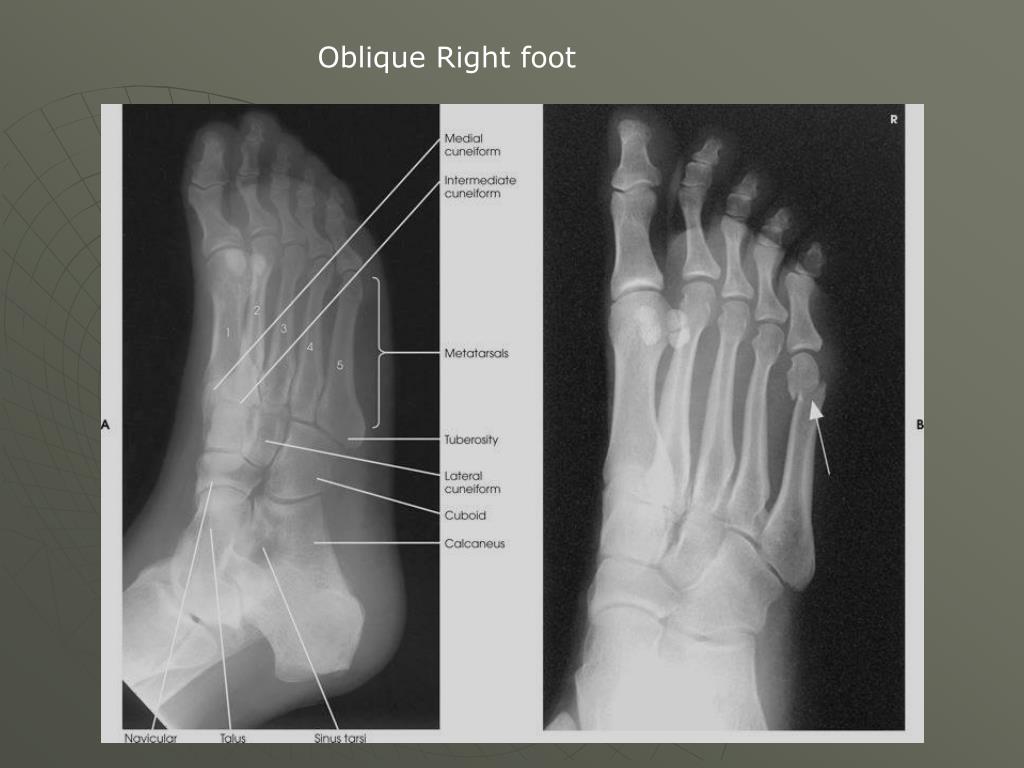

21. Oblique Right foot

22. Oblique Right Foot medioblique

23. Structures shown: • AP medioblique projection of the phalanges and metatarsals • Interspaces open between the cuboid and calcaneus, the cuboid and the 4th and 5th metatarsals, the cuboid and the lateral cuneiform and the talus and the navicular • Cuboid is in profile • Sinus tarsi, calcaneus, navicular,& base of the fifth are seen

24. Oblique Left Foot Calcaneus?

25. Check for: • Enough rotation when the 3rd – 5th metatarsals bases are free from superimposition • The lateral tarsals with less superimposition than in the AP • Joint spaces open • Base of the fifth metarsal is seen • Density: are the toes seen and are the tarsal seen • Tip of toes to calcaneus on the image